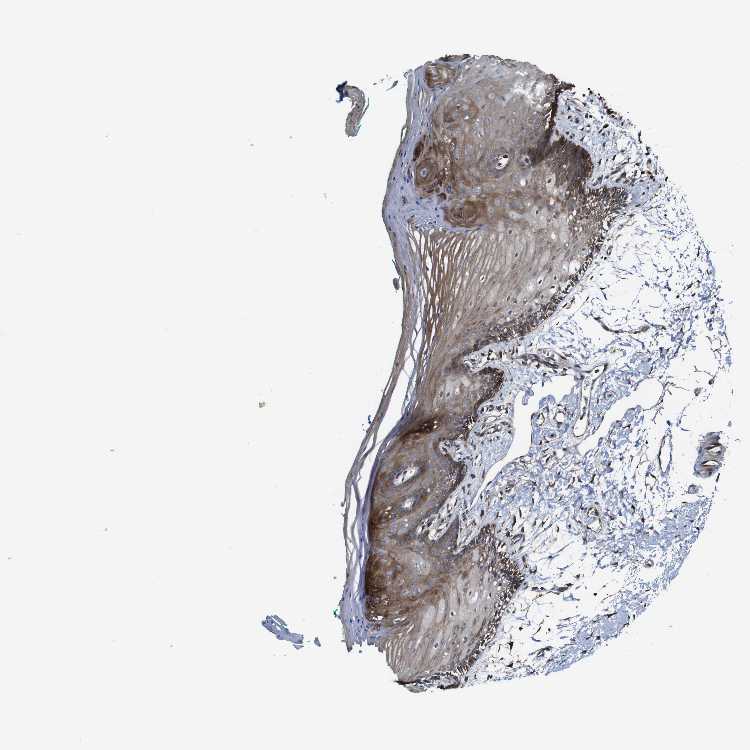

TISSUE PRIMARY DATA ORAL MUCOSA Show tissue menu

ORAL MUCOSA - Antibody stainingi

Antibody staining in the annotated cell types in the current human tissue is reported as not detected, low, medium, or high, based on conventional immunohistochemistry profiling in selected tissues. This score is based on the combination of the staining intensity and fraction of stained cells.

Each image is clickable and will lead to virtual microscopy that enables deeper exploration of all samples and also displays staining intensity scores, fraction scores and subcellular localization as well as patient and tissue information for each sample.

Antibody HPA013203

Squamous epithelial cells Medium